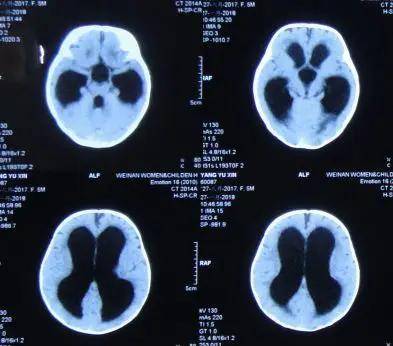

5月龄婴儿脑积水出现头颅增大,双眼落日征,发育迟缓

9天后)入院时:头颅增大,精神不好,时常哭闹,眼睛初有落日征症状(图-3)

「落日征」:因为上注视麻痹,眼球自然下沉,形如落日(如下图).

眼睛会表现为"落日征",患儿的眼球会下垂至眼睑的下方,并且眼睛的大

主要有颅内压增高症状,头围异常增大,前囟扩大,落日眼征等